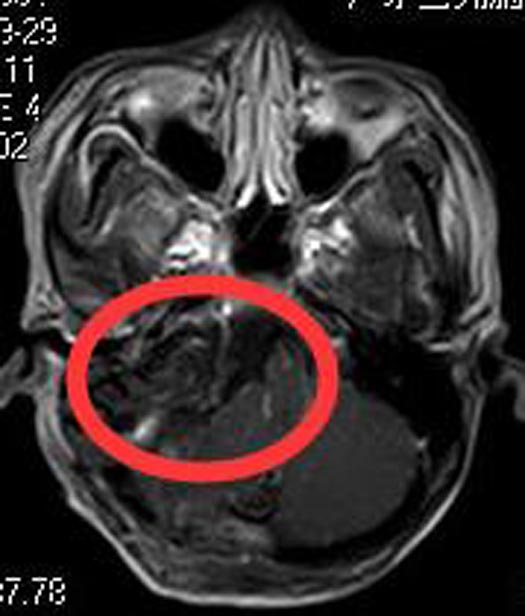

入住广东三九脑科医院综合神经外科,头颅MR检查结果:右侧桥小脑角区占位性病变4.5cm×3.6cm×5.7cm,增强后呈不均匀明显强化,向下达颈静脉孔区;邻近脑干、右侧桥臂及小脑半球明显受压移位。头颅CTA检查提示:右侧桥小脑角区肿块,突入右侧扩大的内听道,并沿扩大颈内静脉孔向颅外蔓延,其血供丰富,周缘较多血管缠绕,邻近椎基底动脉受压移位。

考虑肿瘤血供丰富,术前脑血管造影+肿瘤部分供血血管栓塞术。由鲁明主任主刀,在全麻下行右侧颈静脉孔区颅内外沟通肿瘤切除术,显微镜下见红褐色肿瘤组织位于右侧颈静脉孔区(硬膜外),质中,包绕右侧舌咽神经、迷走神经、副神经,利用剥离子、双极电凝、超声刀等分块全切肿瘤,术中全程电生理检测,面、听、三叉神经保留完好。术后病理结果:神经鞘瘤。